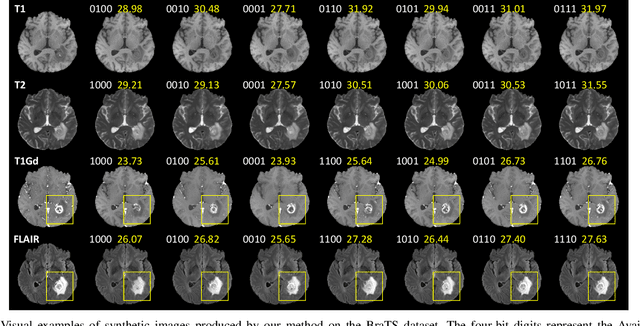

Abstract:Multi-modal medical images provide complementary soft-tissue characteristics that aid in the screening and diagnosis of diseases. However, limited scanning time, image corruption and various imaging protocols often result in incomplete multi-modal images, thus limiting the usage of multi-modal data for clinical purposes. To address this issue, in this paper, we propose a novel unified multi-modal image synthesis method for missing modality imputation. Our method overall takes a generative adversarial architecture, which aims to synthesize missing modalities from any combination of available ones with a single model. To this end, we specifically design a Commonality- and Discrepancy-Sensitive Encoder for the generator to exploit both modality-invariant and specific information contained in input modalities. The incorporation of both types of information facilitates the generation of images with consistent anatomy and realistic details of the desired distribution. Besides, we propose a Dynamic Feature Unification Module to integrate information from a varying number of available modalities, which enables the network to be robust to random missing modalities. The module performs both hard integration and soft integration, ensuring the effectiveness of feature combination while avoiding information loss. Verified on two public multi-modal magnetic resonance datasets, the proposed method is effective in handling various synthesis tasks and shows superior performance compared to previous methods.